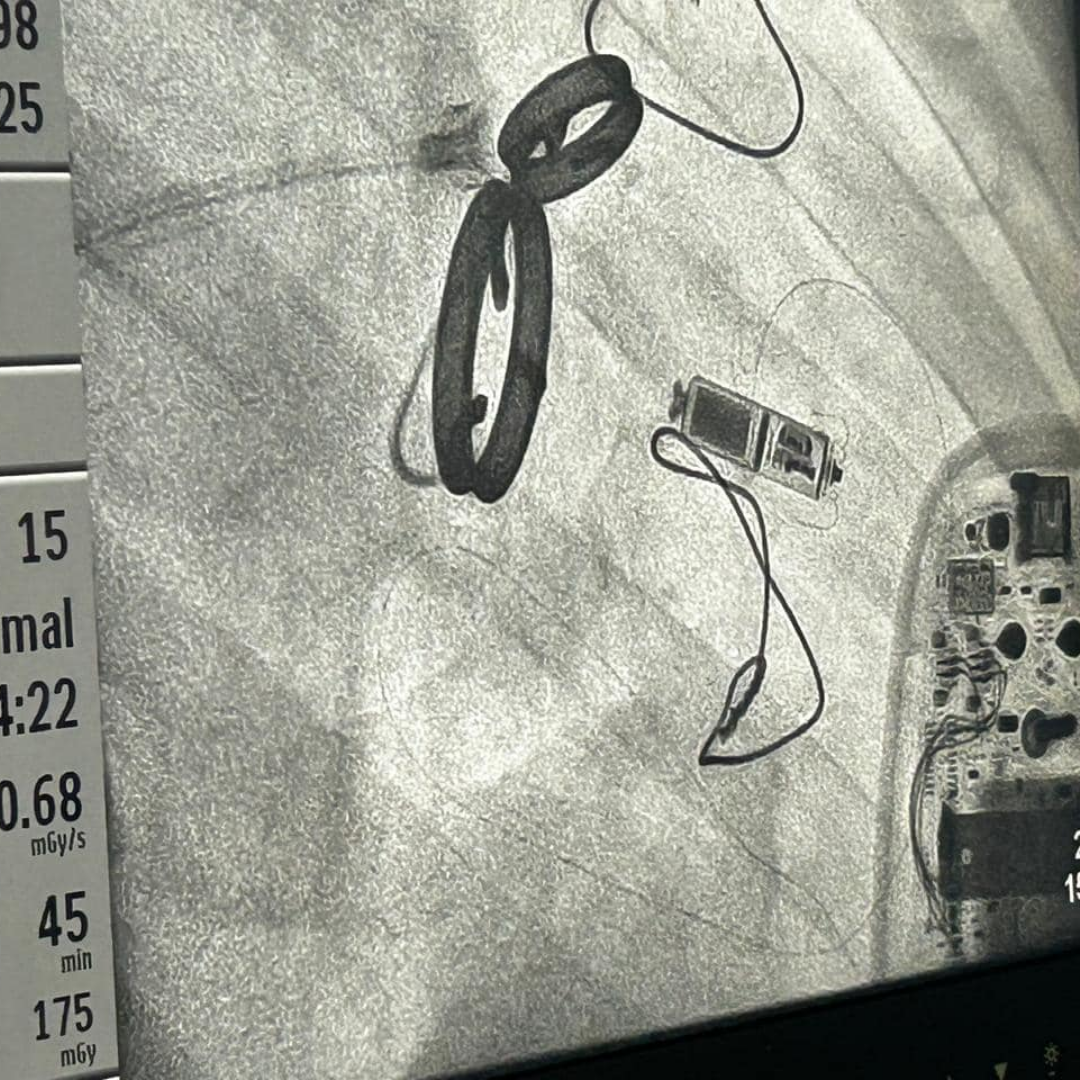

Dr. Dilip Kumar Leads the Way with Eastern India's First Aveir Leadless Pacing Capsule Cases at Medica

Milestone Achieved: First Micra AV Procedure in Jharkhand at Medica Ranchi